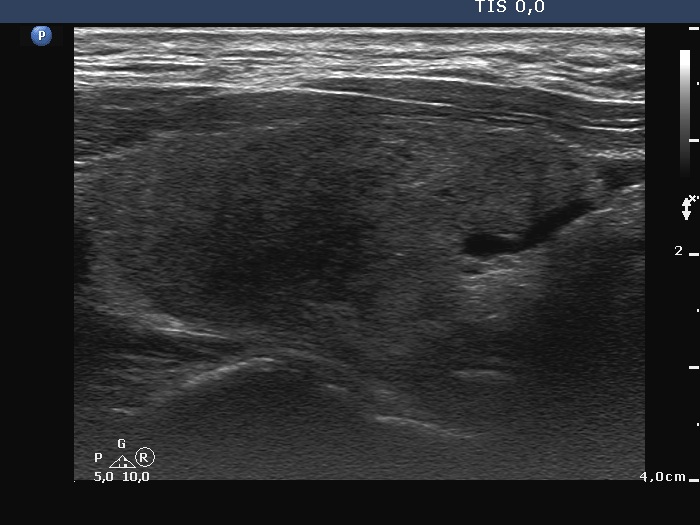

Examination a year after the first visit (third row of images):

Clinical presentation: The patient had no complaints.

Palpation: no abnormality.

Laboratory tests: TSH 1.60 mIU/L, FT4 15.6 pM/L, aTPO 12 U/mL.

Ultrasonography: The dorsal part of the right lobe remained hypoechoic. The nodule in the left lobe has increased in size and presented halo and signs of perinodular vascularity.

Cytology of the nodule resulted in benign lesion.

Suggestion: repeat examination in three years.

Comment. In the active phase of subacute thyroiditis, a nodule can be obscured. The real structure of the thyroid can be revealed only when the hypoechogenicity disappears or decreases significantly.